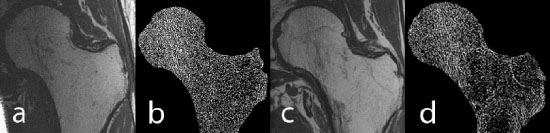

High-resolution MRI of the hip: a) image of a healthy male control, b) trabecular structure after fuzzy thresholding, c) image of an age-matched HIV-infected male subject, d) trabecular structure of the HIV-infected scan. Trabecular structure is less dense in the HIV-infected subject, in particular in the neck, trochanter, and shaft.